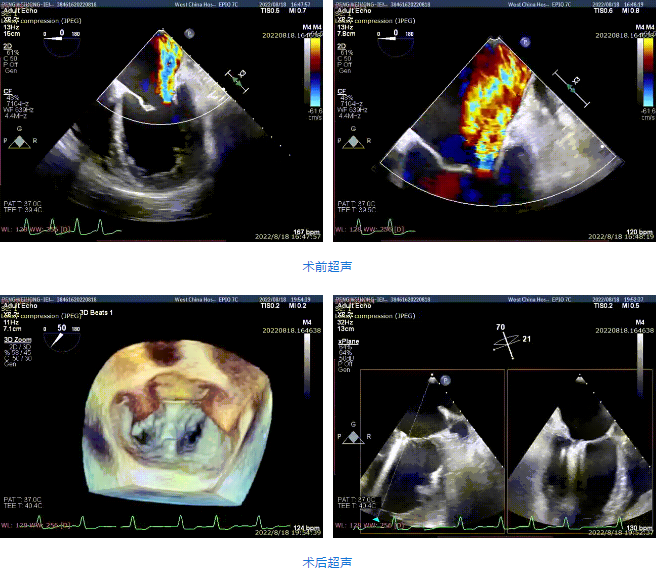

接受治療的是一例59歲男性患者,主訴“心累氣促5余年,加重伴胸痛1個多月”,已經(jīng)過規(guī)范化藥物治療。術(shù)前超聲提示左心明顯增大,右心稍大。左室心尖部肌小梁增多。室間隔及左室后壁厚度正常,左室后下壁基底段變薄、稍向外膨出,搏幅明顯減弱,余室壁搏幅減低,左室壁整體運動欠協(xié)調(diào)。二尖瓣瓣尖稍增厚,回聲稍增強,后瓣受牽拉,活動度差,前瓣關(guān)閉錯位,開放尚可。多普勒提示:二尖瓣大量反流(VC=6*18mm,EOA=0.53cm2,Vol=61ml);二尖瓣環(huán)舒張期運動頻譜呈單峰,EF=30%。

手術(shù)采用全身麻醉插管,經(jīng)股靜脈-房間隔入路,在TEE和DSA引導下完成房間隔穿刺。置入瓣膜夾系統(tǒng)后,在左房調(diào)整瓣膜夾的位置和軸向,后進入左室,在TEE引導下捕捉二尖瓣前后瓣葉,并關(guān)閉瓣膜夾。經(jīng)TEE反復確認手術(shù)效果后最終鎖定并釋放瓣膜夾。術(shù)后即刻超聲顯示瓣膜夾位置穩(wěn)定,功能良好,肺靜脈逆流和左房壓都明顯好轉(zhuǎn)。